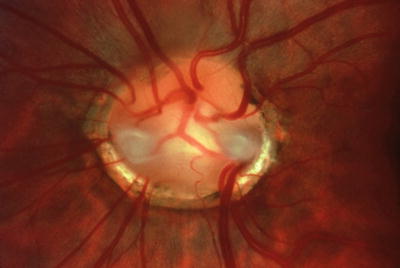

Papillorenal syndrome. The PARSA optic disc is characterized by perturbed angiogenesis, associated renal complications, sans a central retinal artery. Note central excavation with multiple cilioretinal vessels and absence of central retinal vasculature.

Color Doppler imaging has confirmed the absence of central retinal circulation in patients with papillorenal syndrome [286]. Visual acuity is usually 20/20 but may occasionally be severely diminished secondary to choroidal and retinal hypoplasia and, in some cases, to late-onset serous retinal detachments [286]. Peripheral visual field defects corresponding to areas of retinal hypoplasia are often present. The central optic disc excavation and peripheral field defects can simulate coloboma as well as normal-tension glaucoma. Follow-up examination has shown renal disease in some patients who were originally reported as having isolated familial autosomal dominant coloboma [286, 323]. In infants, the bilateral optic disc excavation can simulate congenital glaucoma, but the diagnosis can be established clinically by recognizing the characteristic optic disc morphology [217].